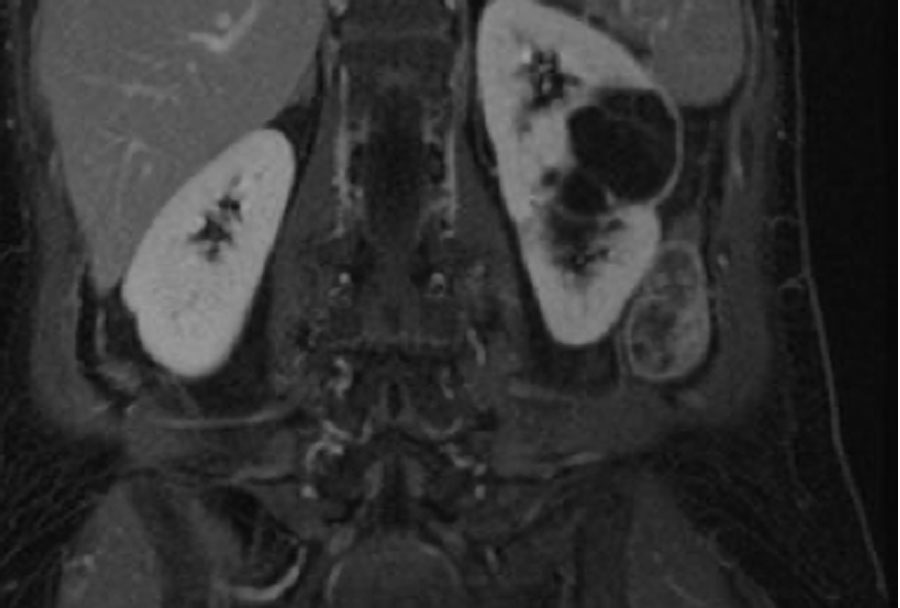

Các ảnh T2W mặt phẳng axial và coronal cho thấy một tổn thương dạng nang ở cực dưới thận trái với thành dày không đều.

Do thành phần mô đặc chiếm dưới 25% tổn thương, tổn thương cần được phân loại là khối dạng nang thay vì u thận đặc dạng nang.

Trên các ảnh T1W coronal có ức chế mỡ trước và sau tiêm thuốc tương phản từ, độ dày thành đo được trên 4 mm (mũi tên).

Tổn thương được phân loại là khối dạng nang Bosniak IV.

Khối đã được phẫu thuật cắt bỏ và được xác nhận là ung thư biểu mô tế bào sáng.